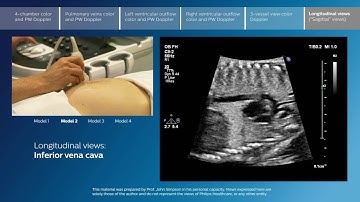

Advanced screening views of the fetal heart - Part 5 - 3-vessel view color Doppler